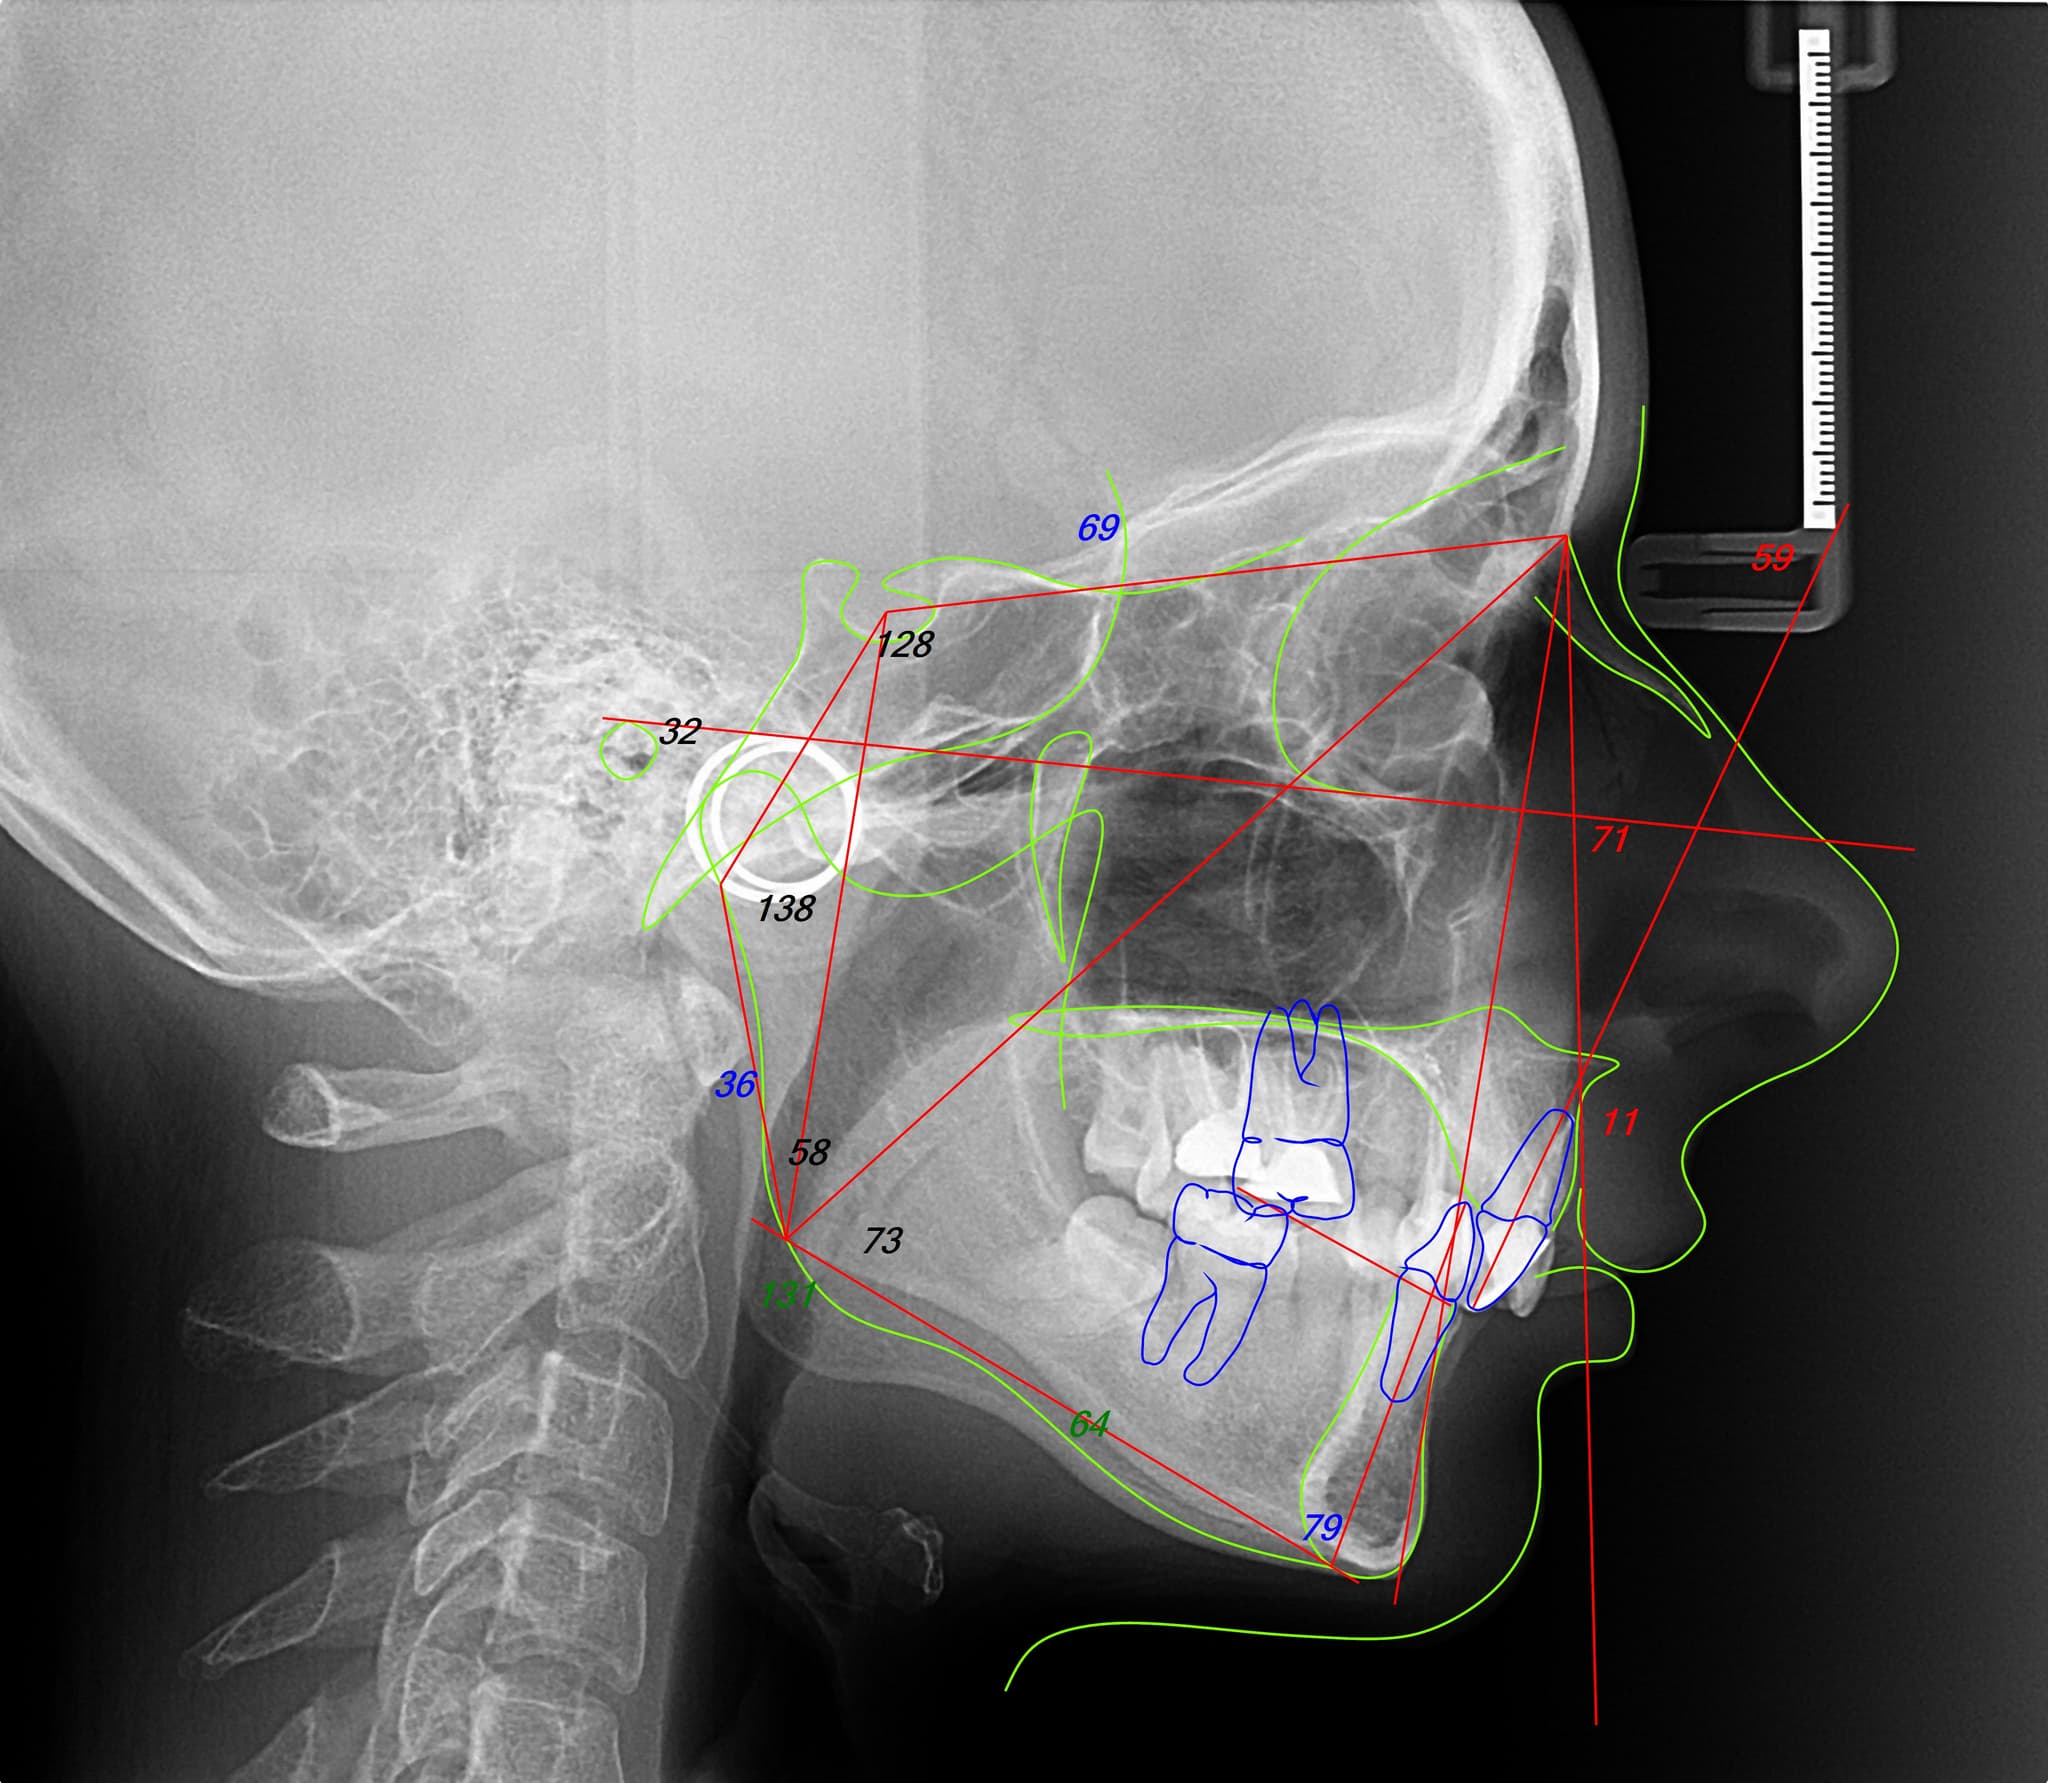

1. Diagnostic and Planning

Design before movement.

Each orthodontic case begins with a complete digital analysis: facial photos, bite scans, and jaw position. From there, we build a single interdisciplinary plan, aligning orthodontics with the broader treatment goals—be it prosthetic, surgical, or periodontal. This layered but unified approach ensures that every movement serves a long-term, integrated outcome.

Facially driven planning.

We never treat teeth in isolation. Your facial structure, expressions, and muscle dynamics shape the entire orthodontic plan. This allows us to move teeth with intention, aiming for harmony instead of mechanical perfection.